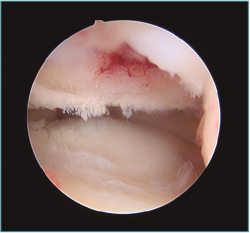

Figura 5. Imagen artroscópica de defecto condral en porción anteroinferior de capitellum. Óptica en portal anteromedial proximal.

Figura 6. Abundante sinovitis y cuerpo libre alojado en cámara anterior en un paciente con lesión osteocondral de tipo IV de la International Cartilage Repair Society (ICRS).